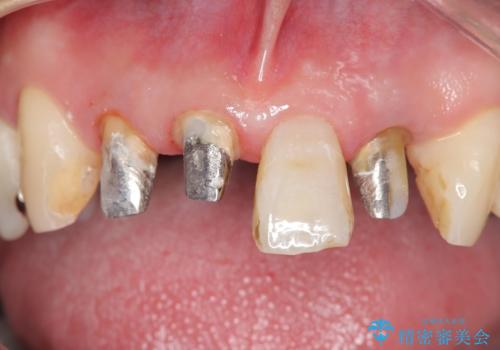

古い被せ物を除去しオールセラミッククラウンで治療を行いました。

被せ物の適合が悪く劣化もおこし色が変色している状態でした。そのため他の歯とも色が合っていませんでした。古い被せ物を除去し形を整えた後にオールセラミッククラウンで治療を行いました。

根っこの先端に病巣(根尖性歯周炎)があったため根管治療または抜歯してインプラントを提案しましたが、患者さんのご希望により被せ物の治療のみを行いました。